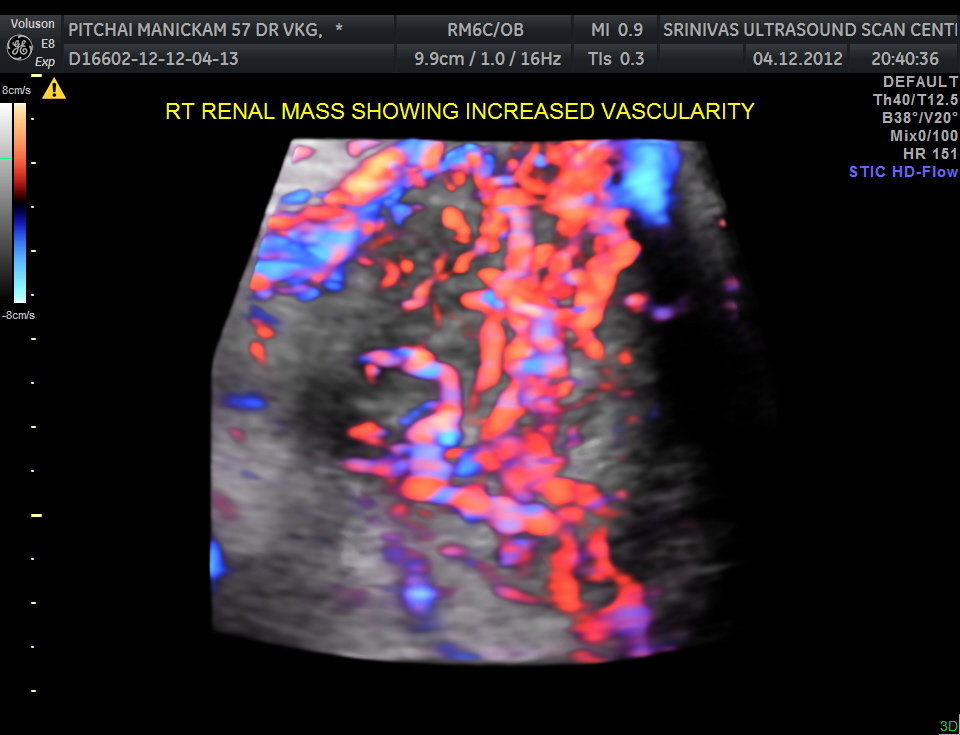

The right renal mass shows increased vascularity .

The images are presented to show the increased vascularity on colour Doppler and the lobularity seen in the reconstructed image and also for the clinical presentation of pain on the contralateral side due to herpes zoster.